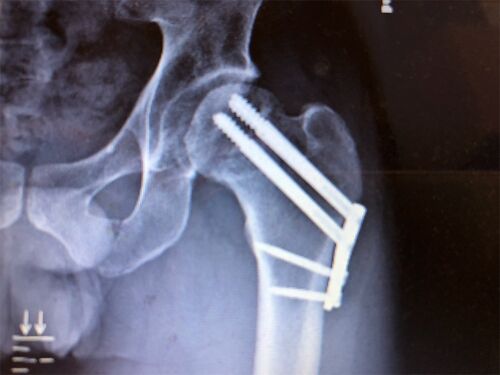

毎日恒例 リハ室で一人絶叫 動きの練習をする前に動かす場所を触診して、視神経のチェックと不具合を探ってくれるんだけど、この時少しでも異変というか筋肉の固着を発見した場合容赦なくその箇所を潰しにかかってくださいと伝え、自分がイタタタとかうおー…